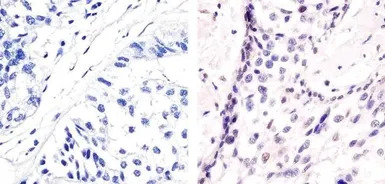

IHC-P analysis of human breast carcinoma tissue using GTX24736 ATF2 (phospho Thr71) antibody.

Right : Primary antibody

Left : Negative control without primary antibody

Antigen retrieval : 10mM sodium citrate (pH 6.0), microwaved for 8-15 min

Dilution : 1:20